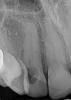

(7.) Radiographic presentation of ECR in tooth No. 22. Note the distal-cervical portal of entry and how the shape of the root canal is visibly distinct from the resorptive lesion.

Figure 7

When using periapical radiographs in diagnosis, external resorptive defects should appear to move when captured from differing angulations and will have a visible and intact pulp chamber in all but advanced cases.1 All radiographic findings can help to differentiate ECR lesions from internal root resorption lesions, which have symmetrical, smooth, and clearly defined walls that appear to balloon out from the pulp chamber and do not appear to move with multiple parallax images. Conversely, ECR lesions have a less defined, irregular, and "ragged" or "moth-eaten" appearance and demonstrate variations in density, which makes them distinct from internal root resorption lesions that are usually uniform in density (Figure 7).2,14

On radiographs, early ECR lesions may exhibit a diminutive spot at the cementoenamel junction (CEJ), which may be confused with cervical burnout, but throughout the majority of the lesion, the root canal should be visible and intact. Advanced ECR lesions will appear as large radiolucent areas with less well-defined or "moth-eaten" borders that can extend into the pulp space.25 If an ECR lesion is in the repair-remodeling stage of development, it may appear more radiopaque due to the ossification of granulation tissue. Radiopaque spots may also be observed due to disruption of the PRRS that has led to local calcification of pulp tissue.6